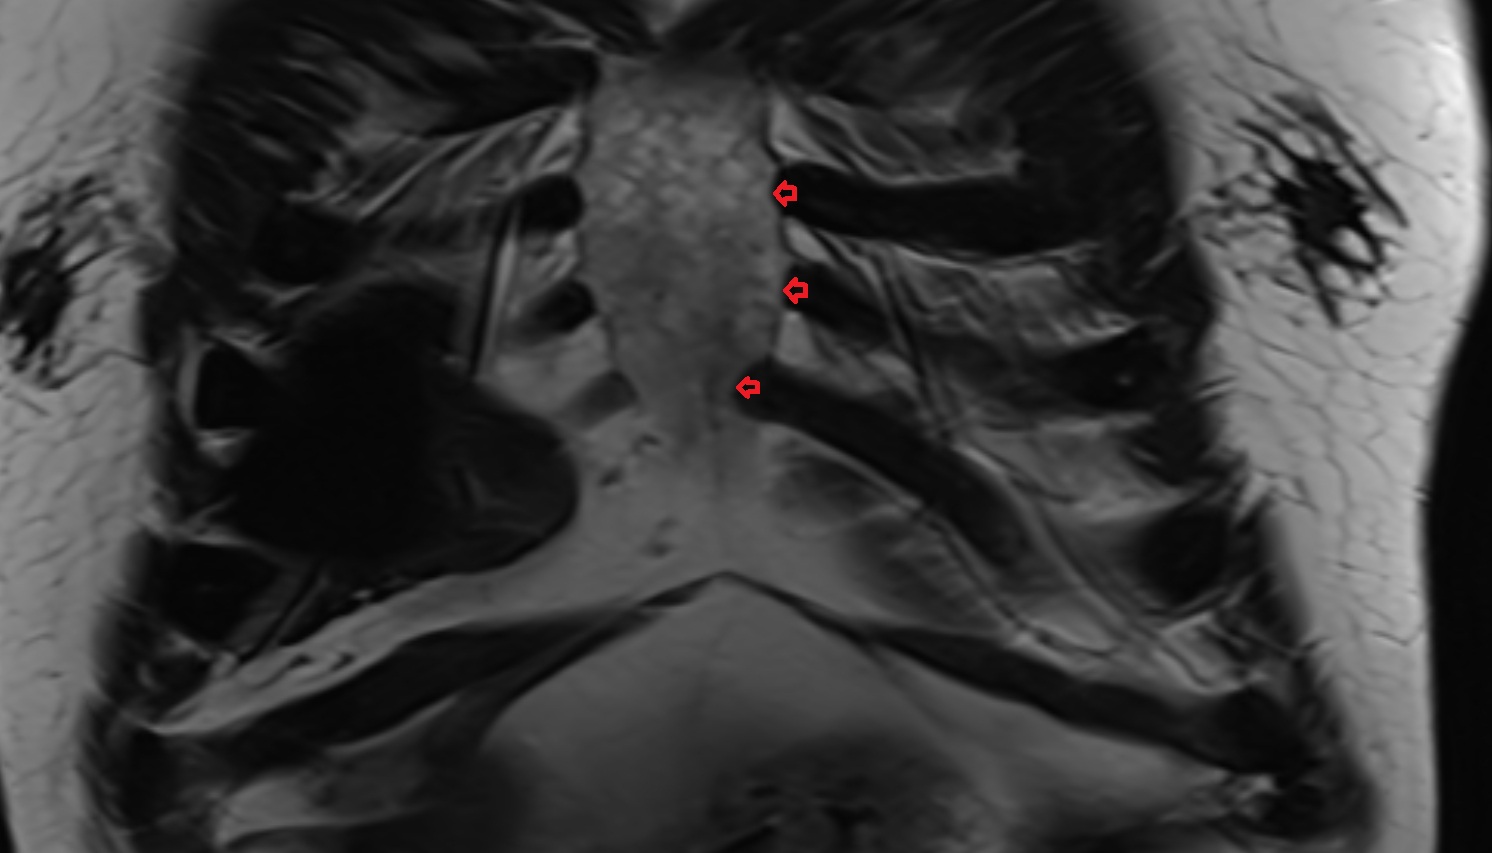

- Manubrium of sternum

- Body of sternum

- Xiphoid process of sternum

- Sternum